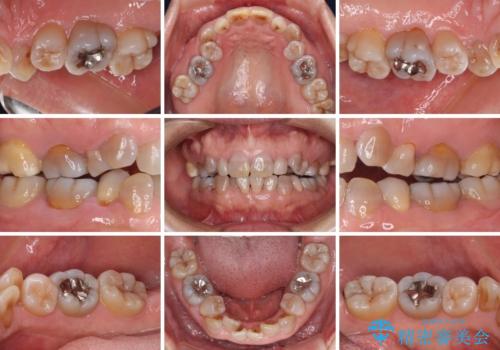

- 小さいころからの歯の変色と矯正治療の後戻りを気にして来院された患者様です。

気になる変色歯を仮歯に変え、その後歯列不正を矯正治療で改善し、最後にオールセラミッククラウンにて補綴治療することとしました。